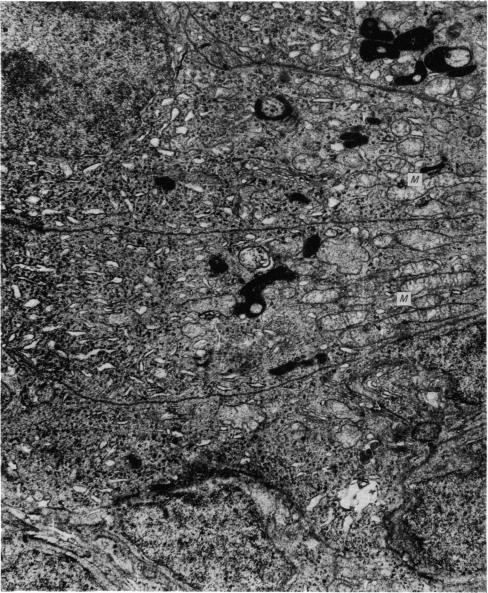

The pineal gland of chicks treated with oestrogens and androgens has been studied histochemically and ultrastructurally from post-hatching until 90 days of age. The results obtained may demonstrate a precocious maturity of the gland caused by its response to the early high level of sex hormones circulating in the blood.

对用雌激素和雄激素处理过的雏鸡的松果体进行了组织化学和超微结构研究,研究从雏鸡孵化后直至90日龄。所获得的结果可能表明,由于松果体对血液中早期高水平性激素的反应,该腺体出现早熟。